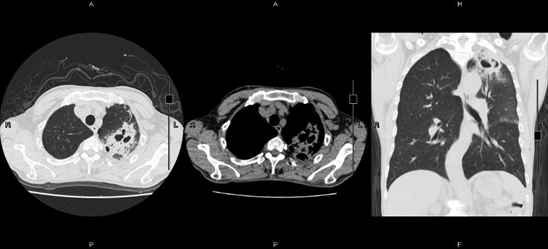

4月27日复查胸部CT示:左上肺动脉、前段动脉及右下肺动脉、后外基底段动脉附壁血栓形成,较前缩小,左肺上叶炎症,左肺上叶尖后段炎症并空洞形成,较前进展(图2),予盐酸莫西沙星0.4 g ivdrip抗感染、化痰解痉等治疗。为求进一步诊治收入我科。起病来,无持续头痛、头晕、胸痛、胸闷、腹痛、腹泻,无双下肢再次浮肿。患者精神一般,胃纳如上述,睡眠可,二便正常,近期体重无明显改变。

图2  患者胸部CT(2018年4月27日)

注:左肺上叶炎症并空洞形成